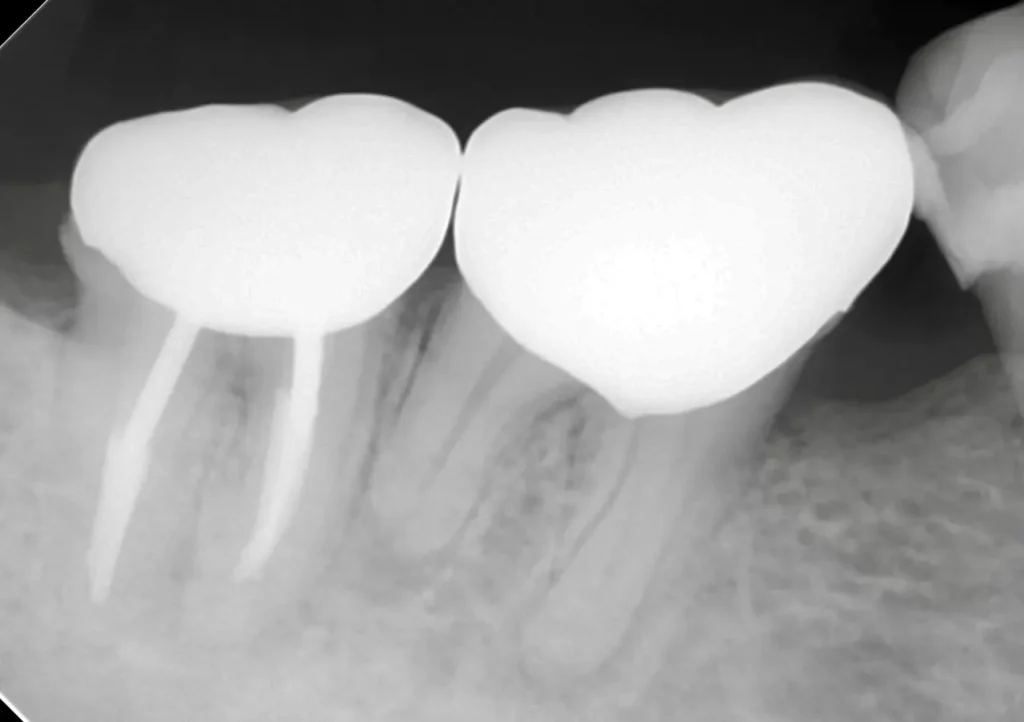

術中

穿孔部分の封鎖と通常の根管治療を行いました

術後

症状は、完全に消えて、穿孔部分の封鎖と確実な清掃、充填が確認できます